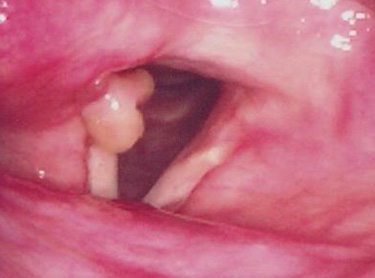

육아종은 접촉성 육아종과 삽관육아종 두 가지로 나뉘며,

피열연골의 성대돌기 부위의 점막과 연골막에 염증이 발생하고

인후두 역류에 의해 악화되어 형성하게 됩니다.

성대육아종은 접촉성 육아종과 삽관 육아종이 있습니다. 접촉성 육아종은 지나치게 낮은 톤으로 음성을 과도하게 사용하거나 만성적인 기침,

습관적 헛기침, 인후두 역류 등으로 발생하게 됩니다. 주로 남성에게서 발생하고 주증상은 애성과 인후두의 통증, 이물감 등을 호소하게 됩니다.

삽관 육아종은 후두수술이나 기관지경검사, 또는 기관내 삽관술 후에 잘 발생합니다.

주로 여자에서 발생하며, 피열연골의 성대돌기 부위의 점막손상이 생기고 이 손상 부위가 육아종으로 치유됩니다.

이 육아종은 처음에는 점점 커지지만 어느 정도 시일이 경과하면 퇴화하기 시작하고 양측성으로 오는 경우도 많습니다.